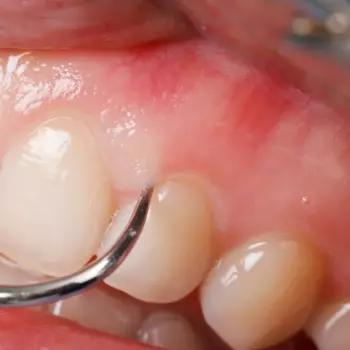

치석은 일 년에 1~2번 정도, 정기적으로 치과를 방문하여 치과 의사의 케어를 받는 것이 좋습니다. 치석 제거는 초음파 또는 치과 전용 치석 제거기 등으로 세세한 부분까지 케어하게 됩니다.